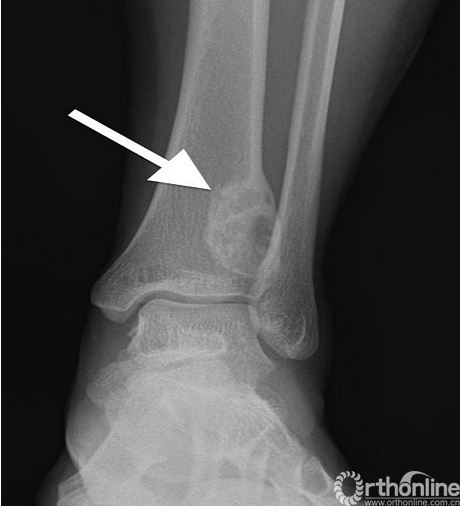

影像学特点:佩吉特病有典型的X线表现,粗大的骨小梁,增厚的骨皮质及病变骨直径的增大(图11)。疾病的进展典型的表现为先溶骨性改变后发展为成骨性改变,但大部分是混杂在一起同时进行的。在脊柱侧位片上,椎体四面的骨皮质增厚形成“相框”样外观改变。负重的下肢骨骼,特别是胫骨,在长期病变过程中可能导致弯曲畸形(图12)。

图12. 佩吉特病致胫骨弯曲畸形,长期病变使长骨弯曲变形,也可见皮质增厚和“火焰样”的皮质骨溶解(箭头)。